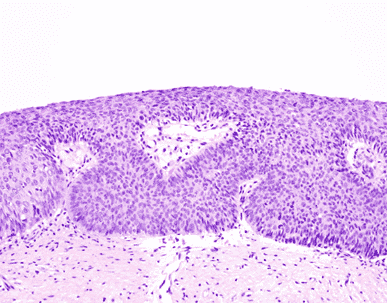

HPV infection may lead to the development of a low-grade (CIN 1) or high-grade squamous intraepithelial lesion (CIN 2 or 3). LSIL development may follow infection by low-risk or high-risk HPV and is thought to depend somewhat on the specific cell population infected (e.g., high-risk HPV infections in the ectocervix, away from the transformation zone, may produce an LSIL-type lesion). LSIL may present colposcopically and microscopically as a flat lesion (Figure 3) or as an exophytic condyloma (Figure 4).

Figure 3

Histologically, the basal layer is somewhat disordered but cytologically bland. There is maturation toward the epithelial surface, where koilocytes may be prominent (Figure 5).